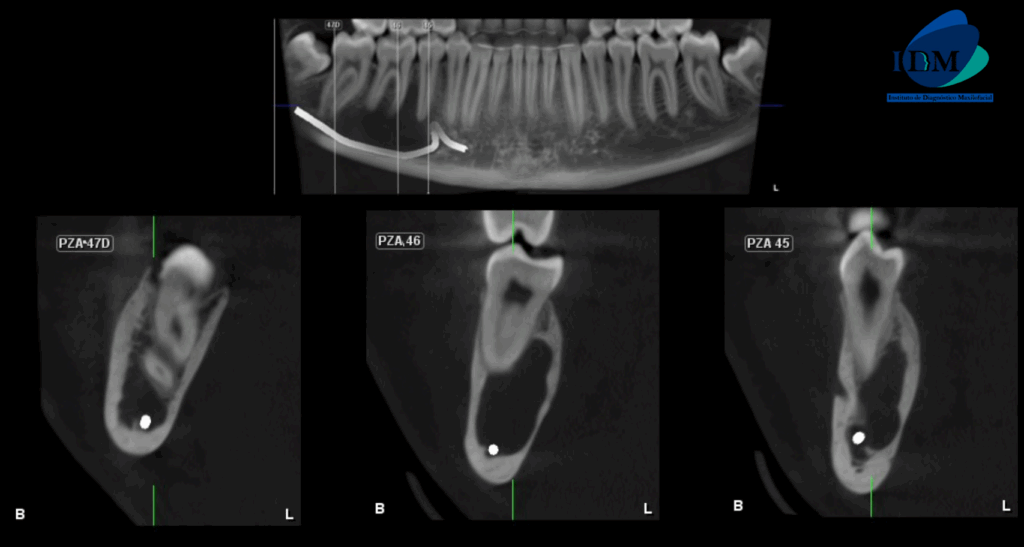

En la radiografía panorámica (Figura 1), se aprecia imagen radiolúcida proyectada en cuerpo mandibular derecho, de limites definidos, bordes parcial mente corticalizados y forma irregular.

A la evaluación de la tomografía volumétrica (CBCT) en los cortes axiales (Figura 2) y transaxiales (Figura 3), se aprecia imagen isodensa de limites definidos, que se extiende en sentido cefálico caudal desde tercio medio radicular de pieza 46 hasta borde basal mandibular, en sentido mesio distal desde mesial de pieza 45 hasta apical de pieza 47, que ocasiona desplazamiento del conducto dentario inferior hacia caudal y borramiento parcial de la cortical superior de la misma, adelgazamiento de tabla ósea lingual.

CORTES TRANSAXIALES